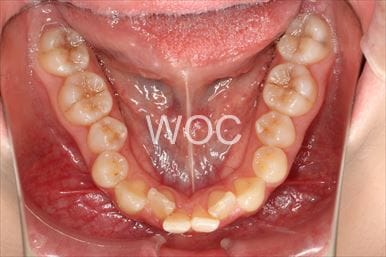

治療前2

治療後2